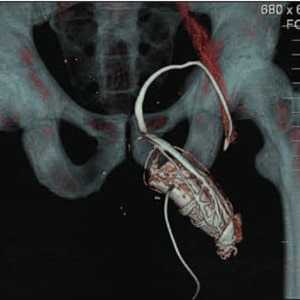

Однако, новые УЗ-технологии опровергают это мнение. Выполнение УЗИ также дает информацию о центральной, периферической части железы и о капсуле. УЗИ с допплеровским картированием, особенно при использовании эхоконтрастных средств, позволяет улучшить визуализацию и распространенность РПЖ (рисунки 2, 3).

Рисунок 2. Возможности 3d-ангиографии при исследовании сосудов предстательной железы